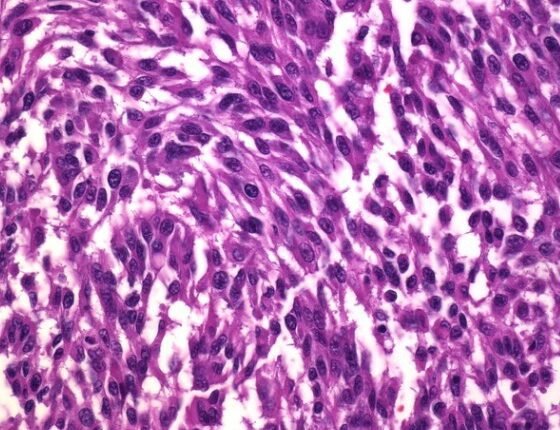

Οι ερευνητές διαπίστωσαν ότι οι HIF1 και HIF2 υπερεκφράζονται σε όγκους μελανώματος. Σε υγιή κύτταρα οι HIF1 HIF2 βοηθούν στη ρύθμιση της υποξίας, της κατάστασης που προκαλείται από τα χαμηλά επίπεδα του οξυγόνου στο αίμα. Η υποξία έχει συνδεθεί με μεταστάσεις σε διάφορους όγκους και η ομάδα του Πανεπιστημίου της Βόρειας Καρολίνας ανακάλυψε ότι προωθεί την εξάπλωση του μελανώματος από το δέρμα σε άλλα σημεία του σώματος, μέσω του λεμφικού συστήματος.

Οι ασθενείς που είχαν διαγνωστεί με μελάνωμα σε αρχικό στάδιο έχουν υψηλό ποσοστό επιβίωσης, αλλά η πρόγνωση χειροτερεύει σημαντικά όταν οι όγκοι εξαπλωθούν σε άλλα σημεία του σώματος. Χρησιμοποιώντας εργαστηριακά συστήματα και με πειραματόζωα ποντικούς οι ερευνητές κατέστειλαν την έκφραση των HIF1 και HIF2 στους όγκους μελανώματος. Παρόλο που η απενεργοποίηση των μεταγραφικών παραγόντων δεν μείωσε την ανάπτυξη των αρχικών όγκων, ωστόσο μείωσε το ποσοστό στο οποίο το μελάνωμα εξαπλώθηκε σε άλλες περιοχές του σώματος.